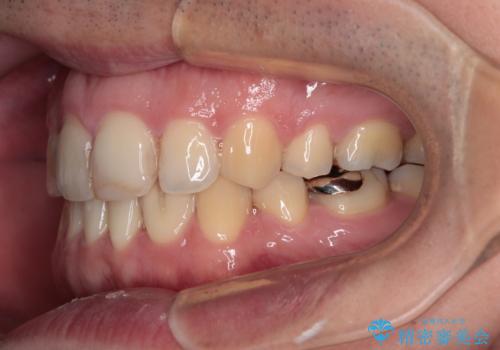

舌突出癖の改善トレーニングは、仕上がり、治療期間、そして治療後の後戻りに大きな影響を及ぼします。

トレーニングをしっかりと行っていただいたため、スッキリとした口元に仕上がりました。